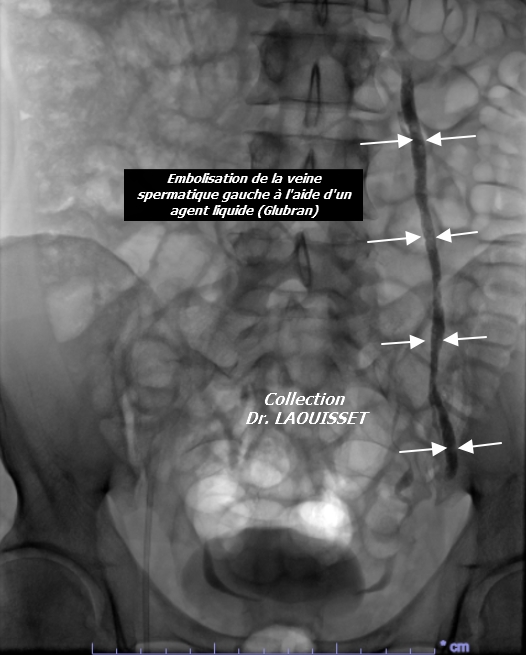

L’embolisation de varicocèle est une procédure mini-invasive qui consiste dans la majorité des cas à occlure la veine spermatique gauche. En effet, cette veine est le plus souvent responsable de la varicocèle, en alimentant les veines péri testiculaires par reflux.

Le principe de l’intervention consiste à introduire dans cette veine, qui est raccordée à la veine rénale gauche, un cathéter. Ce cathéter est dans un premier temps introduit dans une veine du pli de l’aine, la veine fémorale, puis il est dirigé sous rayons X à l’aide d’un guide jusque dans la veine spermatique incontinente.

Une fois installé dans la veine pathologique, un matériel d’embolisation (agent liquide, microspire ou mousse sclérosante) est injecté à travers le cathéter pour entraîner l’occlusion de la veine. Cette occlusion n’est pas néfaste pour le testicule , car d’autres veines assurent son drainage sanguin.